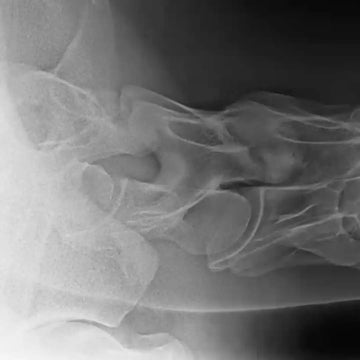

Erfahren Sie in unserem E-Learning Video alles Wissenswerte über die ambulante Röntgendiagnostik der Halswirbelsäule. Lernen Sie alles über die notwendigen Werkzeuge für standardisierte Vorbereitung, die Positionierung des Patienten und die exakte Ausrichtung von Röntgenstrahler und Röntgendetektor.

Zahlreiche Beispielbilder illustrieren die notwendigen Projektionen und zeigen, wie sie präzise angefertigt werden können. Zudem werden typische Pathologien aufgezeigt und ausführlich besprochen. So setzen Sie Ihr Röntgengerät gezielt und effektiv ein!